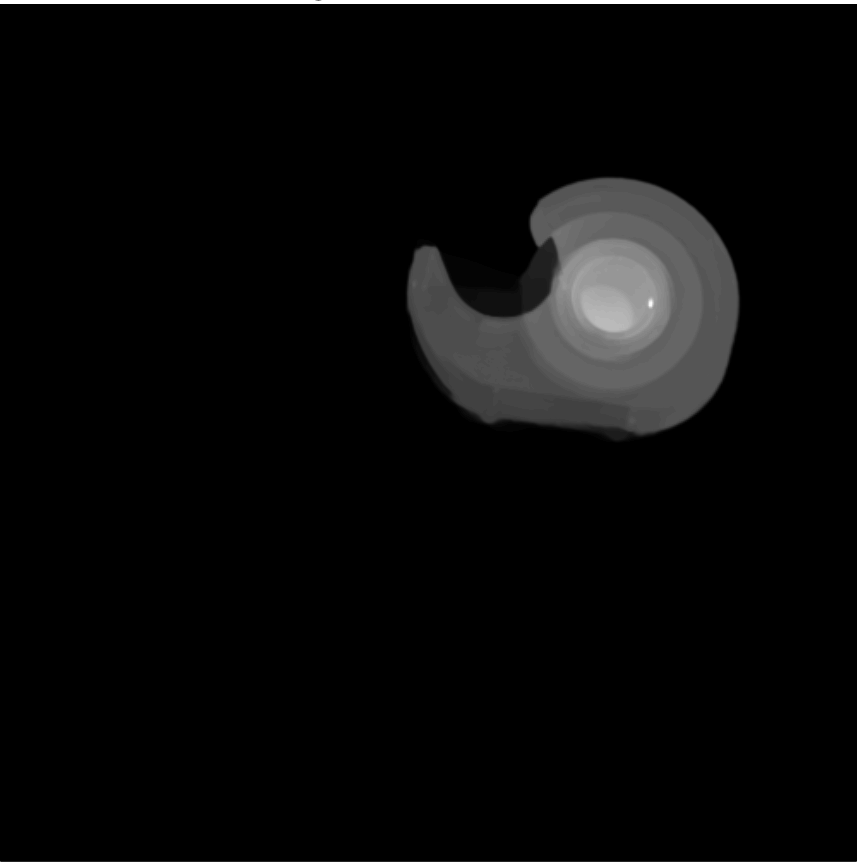

First we will use a Magnetic Resonance (MR) image of a female breast, taken from eby2008magnetic with permission from111www.slicer.org, to segment the tumor mass. On the top/right of Fig. 4, we see the first eigenfunction segmenting the tumor perfectly out of the breast image. Next, in the middle row of Fig. 4, we add to the image , of standard Gaussian noise, such that

where is i.i.d. Gaussian random variable with mean zero, variance equal to one and represents the noise level. Now, we compute the adaptive eigenspace of . Again, the first eigenfunction holds a nice segmentation of the tumor despite the additional noise. To demonstrate the quality of our approach, we consider the image but this time we destroy the boundaries of the tumor and change them by blurring (using an image manipulation program). The resulting image is shown on the bottom left of Fig. 4. On the bottom right of Fig. 4, we see the segmentation is accurate and captures the tumor and its blurred boundaries.

To reduce computational cost and get even more accurate results, we may create a Finite Element (FE) grid on the area of interest rather than on the image boundaries. For illustration, we consider the MR-images and shown on the top/left and bottom/left of Fig. 4, respectively. We automatically produce a mesh on the breast boundaries (see on the left of Fig. 5). The segmentation for and for is shown on the center and right of Fig. 5, respectively.